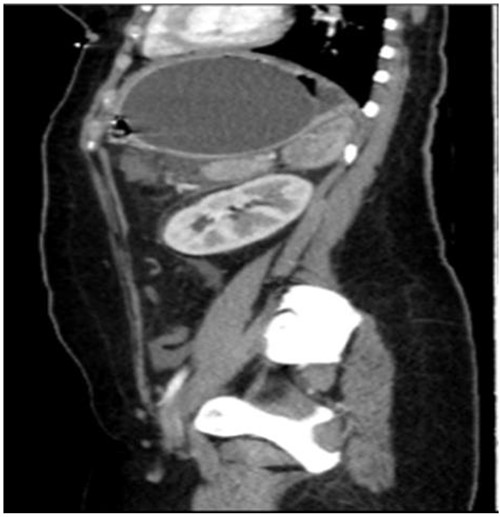

A computed tomography scan with contrast of the abdomen showed gastric fundus distended by a well-defined structure (the balloon) seen compressing the pancreatic body with mild pancreatic tail edema, regional fat stranding and surrounding fluid collection seen tracking to the left perirenal space as shown in Figs 1 and 2. The liver was average in size with no gross contour irregularity or parenchymal abnormal attenuation. No hepatic focal lesion could be detected. Also, no evidence of intra- or extra-hepatic biliary radicle dilatation was detected. A patent average caliber of the portal vein was found, and no porta hepatis lymph nodes seen. No other abnormalities were detected. A magnetic resonance imaging scan was planned but could not be done because the patient had orthodontics (metallic object).

Axial computed tomography (CT) showing IGB compressing the pancreatic body with mild pancreatic edema, regional fat stranding and surrounding fluid collection seen tracking to left perirenal space.